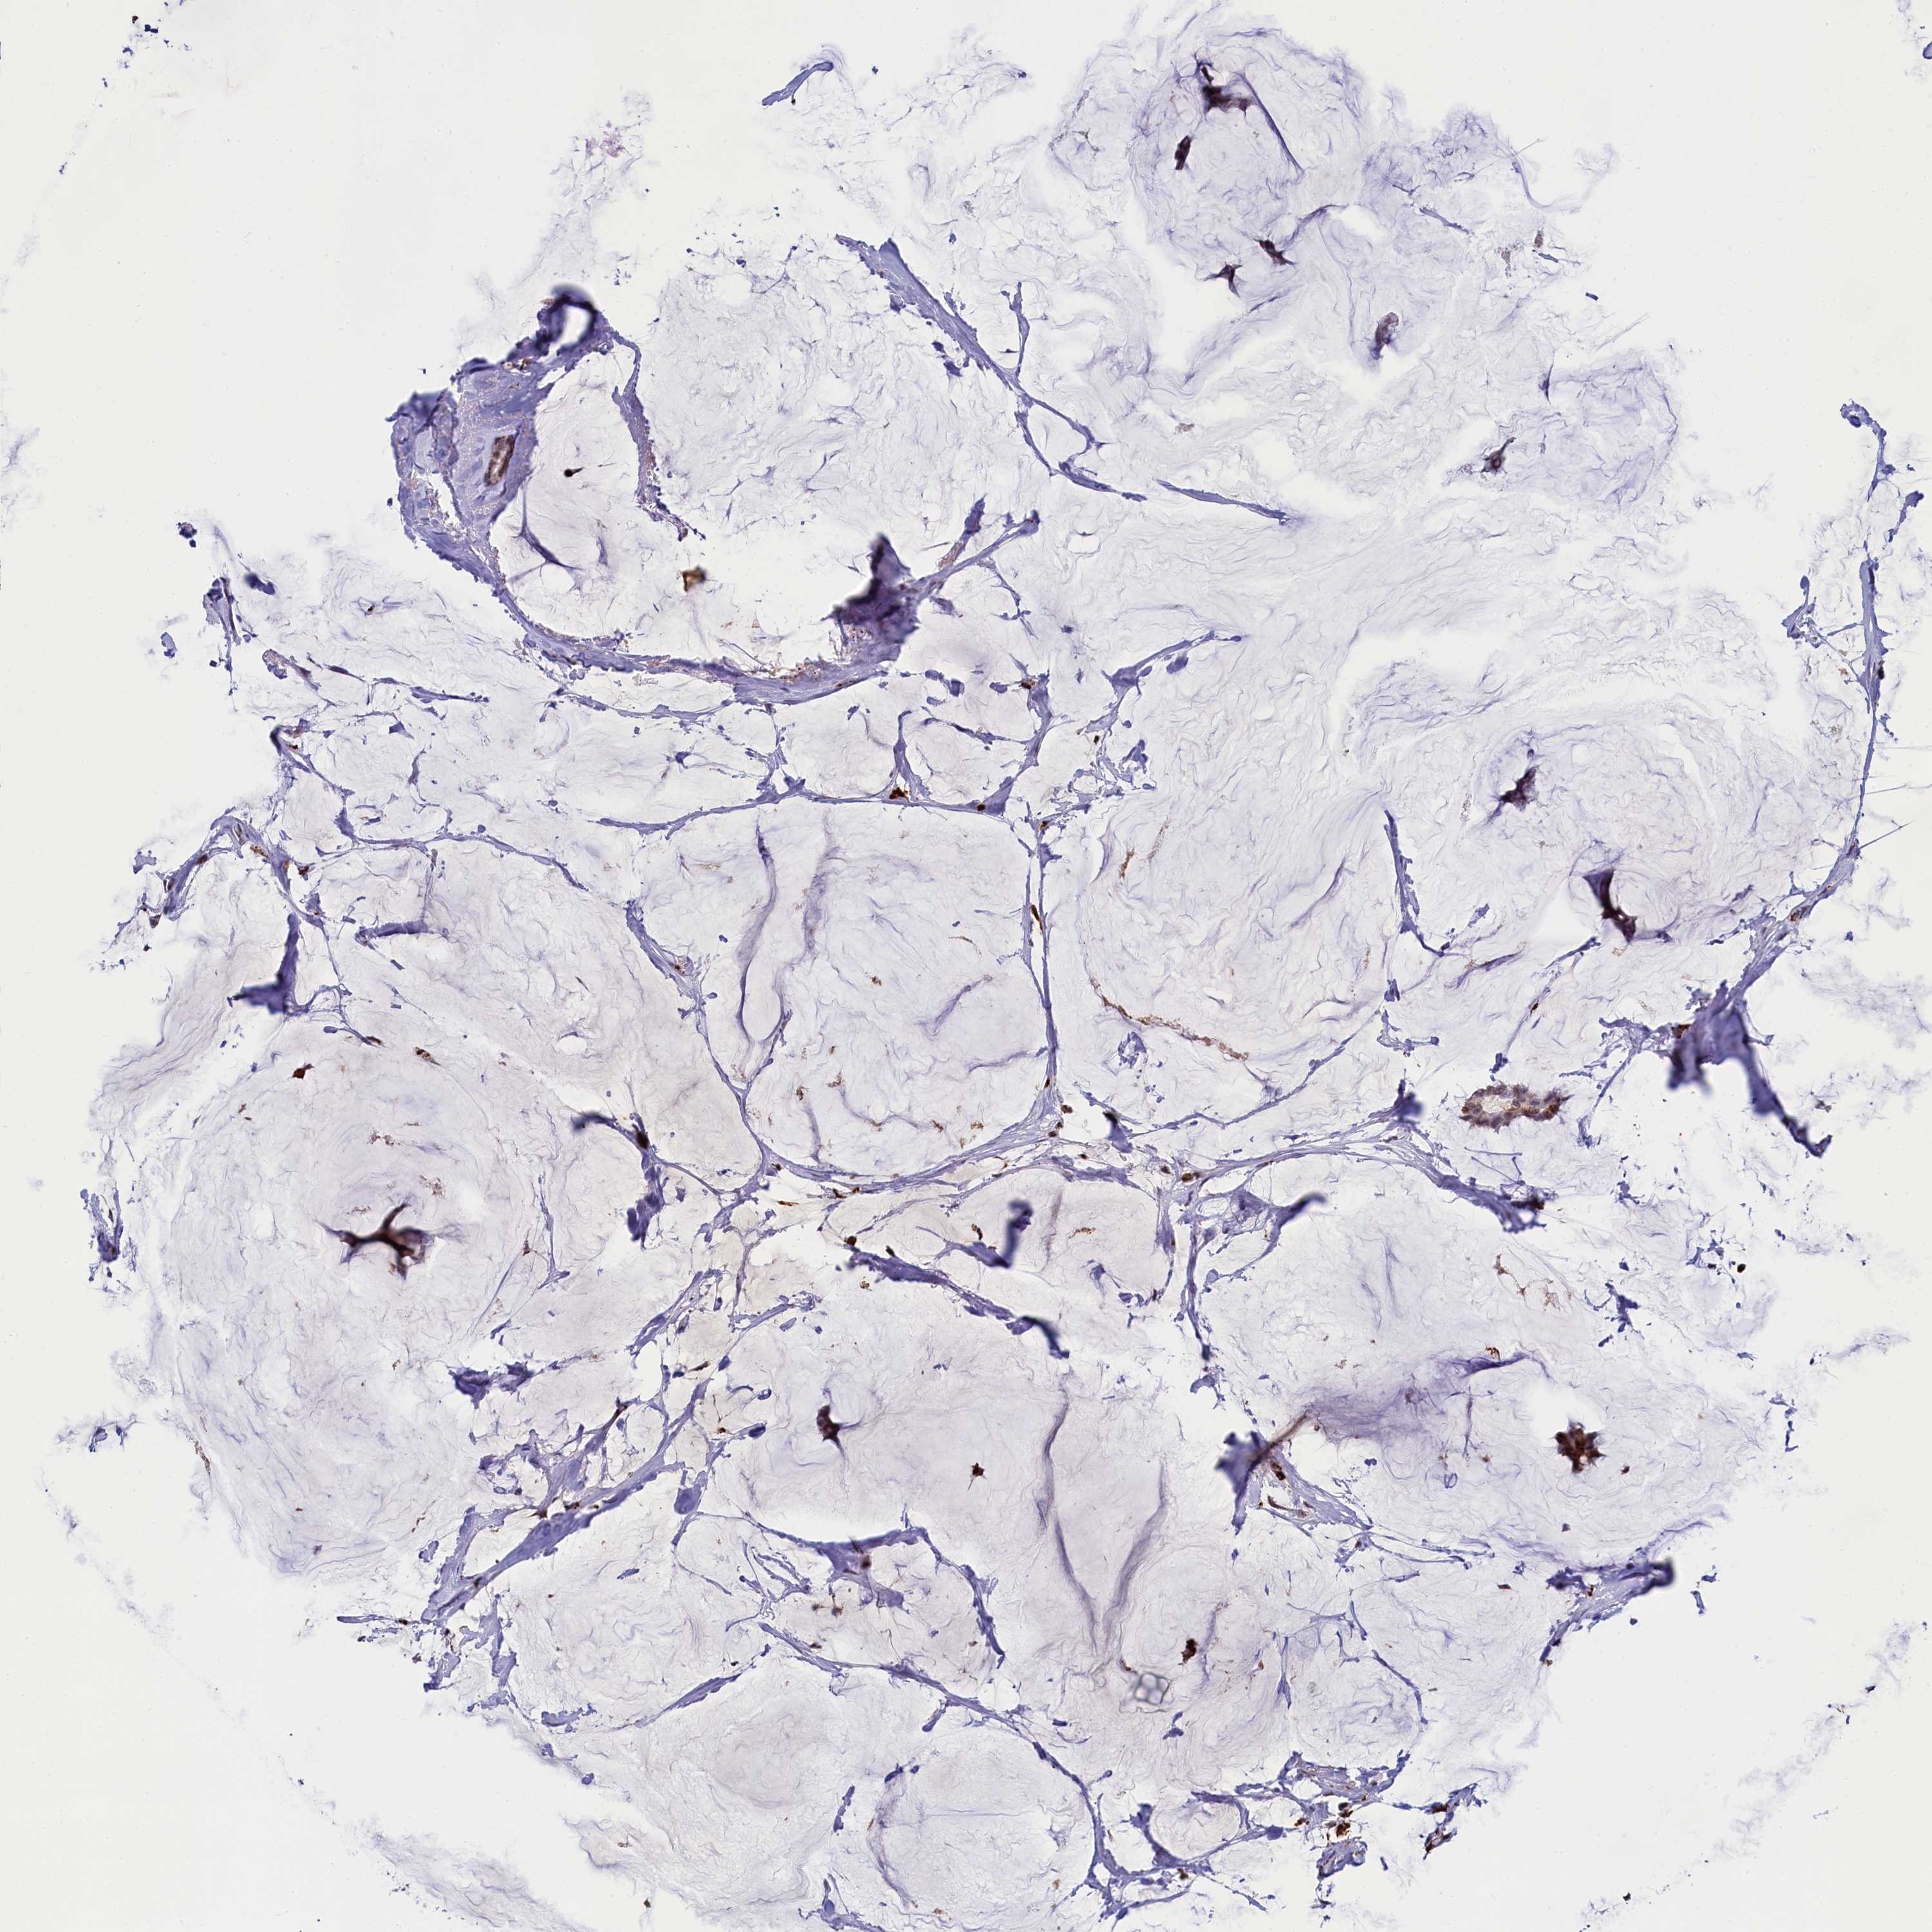

CANCER BREAST CANCER Show tissue menu

BRCA TCGA BRCA VALIDATION PROTEIN EXPRESSION